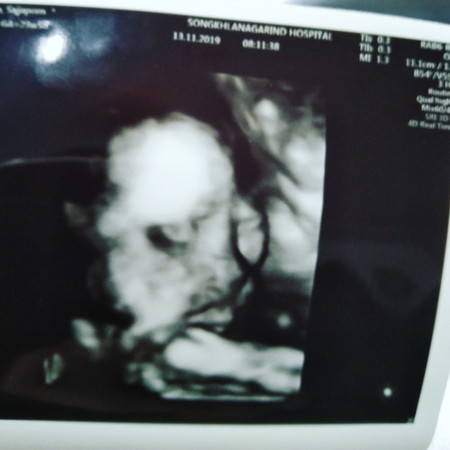

23w5dรกยังเกาะต่ำทำให้น้ำคร่ำน้อย

ลูกสาวค่ะวันนี้เห็นหน้าชัดเลยสุขภาพลูกเเข็งแรงวันนีไปตรวจหาความผิดปกติของร่างกาย. ลูกไม่มีความผิดปกติอะไรเลยค่ะ. แต่คุณแม่รกยังเกาะต่ำอยู่ทำให้น้ำคร่ำน้อย

ดื่มน้ำเยอะนะคะแม่